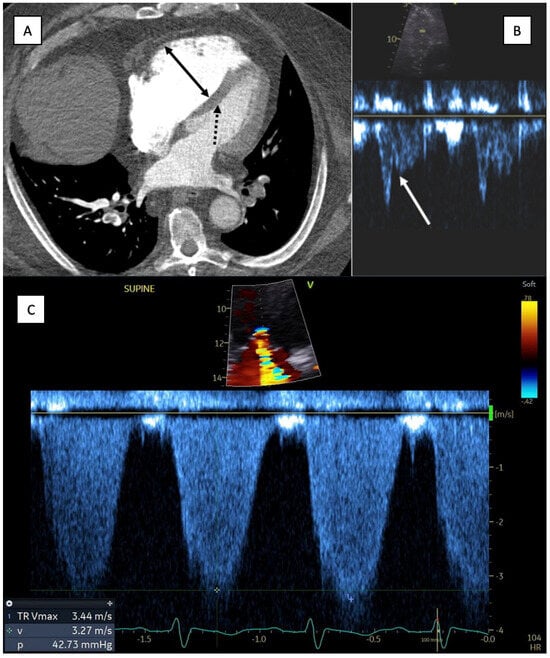

- Lyhne, M.D.; Schultz, J.G.; MacMahon, P.J.; Haddad, F.; Kalra, M.; Tso, D.M.-K.; Muzikansky, A.; Lev, M.H.; Kabrhel, C. Septal Bowing and Pulmonary Artery Diameter on Computed Tomography Pulmonary Angiography Are Associated with Short-Term Outcomes in Patients with Acute Pulmonary Embolism. Emerg. Radiol. 2019, 26, 623–630. [Google Scholar] [CrossRef] [PubMed]

- Becattini, C.; Agnelli, G.; Germini, F.; Vedovati, M.C. Computed Tomography to Assess Risk of Death in Acute Pulmonary Embolism: A Meta-Analysis. Eur. Respir. J. 2014, 43, 1678–1690. [Google Scholar] [CrossRef] [PubMed]